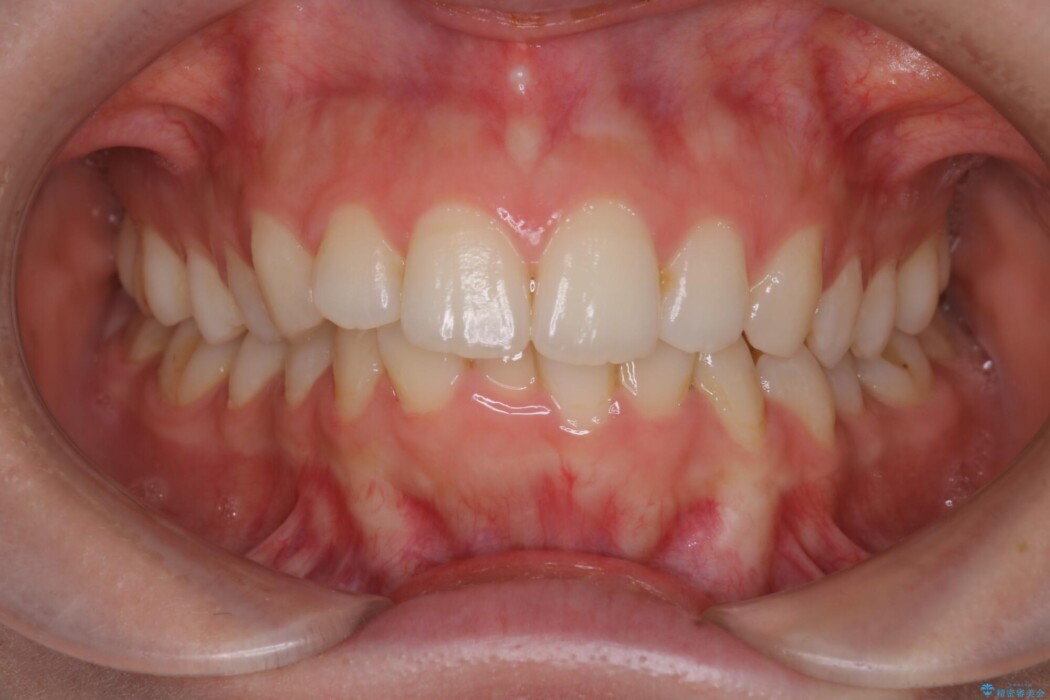

治療後について

マウスピース矯正は22時間以上の装着を推奨しております。

今回患者様にしっかりと装着していただけたため、きれいな歯列へと整えることができました。